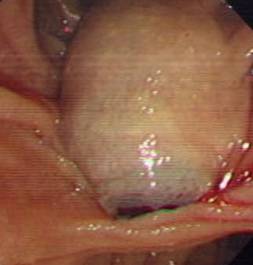

诊疗过程:因重度凝血功能障碍,予以外科手术或内镜下治疗均有发生不可控制的大出血。予以抗感染、保肝及经皮经肝胆囊穿刺引流术等保守治疗3个月,凝血功能有所好转后抓住手术时机,立即行ERCP,术中见结石嵌顿于十二指肠乳头(胆总管末端开口处),立即予以针刀切开十二指肠乳头,顺利取出胆总管结石,解除长达3个月的胆总管梗阻,术后患者很快就拔除胆囊穿刺管,恢复正常生活。

内镜下见结石嵌顿于十二指肠乳头 |